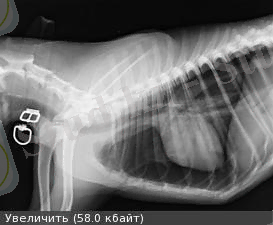

Пневматоракс-потологиялық процесс. Өкпе қаптың висцеральді және париатальді бетінде ауаның жиналуы. Жануарлардың барлық түрінде кездеседі. Ол толық, жартылай, бір және екі жақты, жабық, ашық, клапандық болады.

Этиологиясы . Пневматоракс - операция кезіндегі кеуде қабырғасының сынықтары, оқ-дәрі, ағаш тілімі, мүйіз және басқа заттар малдың кеуде қуысына тигенде туындайды. Ол абсцесстердің ашқанда және өкпе паренхимасы зақымданғанда, туберкулезбен ауырғанда пайда болады.

. Жабық пневматоракста кеуде қуысына енген ауа сорылады содан кейін қалыпқа келеді. Инфекцияланған ауа еніп кетсе, әсіресе, резистенциясы төмен жануарларда ірің түріндегі қабынулар немесе іріңді плеврит дамиды. Кеуде қабырғасында саңылау болса немесе ірі бронхтар жарылса, ауа плевра қуысында еркін кіріп және еркін шықса, ашық пневматоракс пайда болады. Кеуде қуысына ауа енуіне мүмкіндік жасалса, ал ауаның шығуы қиындатылса немесе мүмкін болмаса клапондық пневматоракс дамиды. Пневматоракстың барлық түрінде өкпе ұлпасы қысылады.

Гемоторакс (Haemothorax - қан+ кеуде қуысы) - Плевра қуысында кан жиналу. Қан кұйылуы мен қатар плевра қуысында ауа жиналса, оны гемопневмоторакс деп атайды. Өкпе қан тамырларынан қан кету салдарынан пайда болады. Гемоторакс көп жағдайда кеуде клеткасы жараланғанда болады.